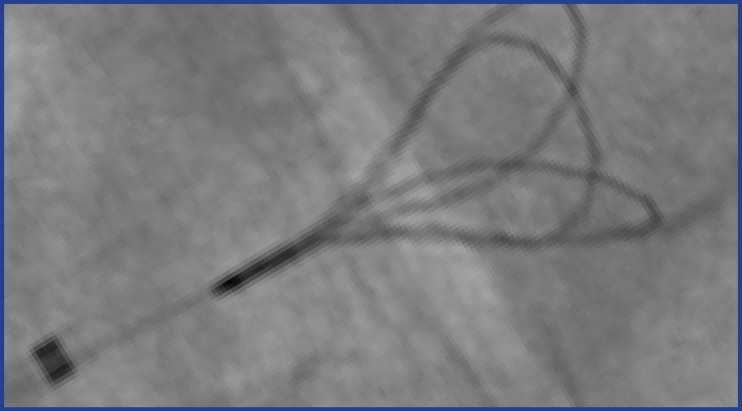

The EN Snare Endovascular Snare System is designed with three interlaced loops to retrieve and manipulate foreign objects in the body. The EN Snare can be used to retrieve inferior vena cava filters, reposition indwelling venous catheters, fibrin sheath stripping, or to assist in central venal access venipuncture. Super elastic Nitinol provides flexibility, kink resistance, and torque control. The EN Snare is designed to rotate and expand for excellent coverage and retrieval within a variety of vessel sizes. Platinum strands are incorporated into the EN Snare loops for excellent visualization under fluoroscopy.

The EN Snare® system consists of three interlaced, cabled, super-elastic Nitinol, preformed loops. The super-elastic Nitinol construction enab

• Interlaced Nitinol Loops designed to resist prolapse and improve capture by allowing the snare to move as a single-unit through the vessel.

• Enhanced Visualization provided by platinum strands incorporated into the loops

• Available in seven configurations with loop diameter sizes ranging from 2 mm to 45 mm.